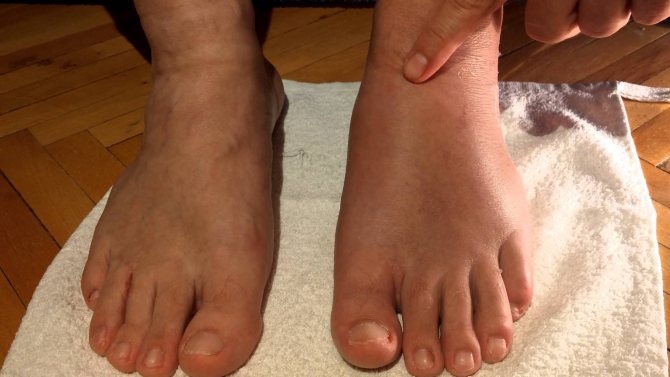

- После разрыва связок голеностопа наблюдается отек тканей в месте травмы. Голеностоп сильно распухает, обретая «слоновый» вид.

Выраженность симптомов зависит от тяжести травмы. Так, при незначительном растяжении пучка волокон пострадавший может не стразу заметить ухудшение состояния. Лишь на 2-3 день после травмы возникнет отек тканей, легкая скованность движений и ноющая боль. Также при 1-й степени разрыва может появиться синяк и жар кожи в области травмы.

После разрыва связок голеностопа 2-й и 3-й степени всегда нарушается подвижность сустава, боль очень интенсивная, ткани отечные. В первые несколько часов связка болит не переставая, а затем боль уменьшается и тревожит только во время движения. Отек быстро распространяется на лодыжку и голень. Посинение кожи может длиться до 10 дней.

Как выглядит разрыв связок голеностопа, фото

В первые часы после разрыва трудно поставить диагноз по внешним признакам. Однако на вторые сутки уже можно отчетливо заметить признаки данной травмы. Понять, что у пострадавшего порваны связки, можно по синеве в месте травмы, обширному отеку, а иногда и по деформации голеностопа, который выкручивается в более удобное положение.

Чтобы знать, как визуально выглядит разрыв связок голеностопа, посмотрите фото: